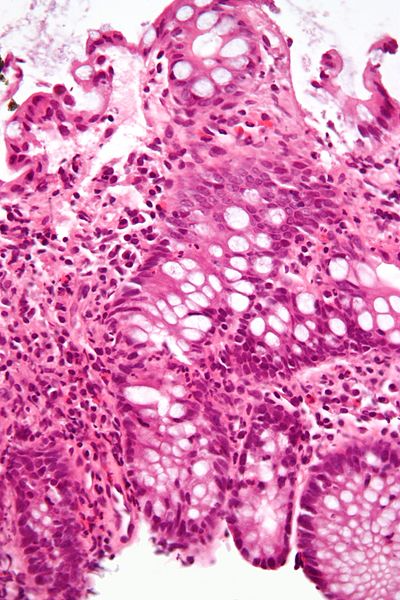

Description: High magnification micrograph of cryptitis in a case of Crohn's disease. H&E stain. Colonic biopsy of the mucosa. The micrograph show numerous neutrophils within the crypt and several eosinophils. The findings in this image (alone) are not diagnostic for Crohn's disease.

The deep aspect of the biopsy has larger hyperchromatic, i.e. darker staining, nuclei, as is typical of the crypt base. The nuclei "mature", i.e. get smaller and less hyperchromatic, toward the superficial aspect; this is a normal finding, which is often absent in dysplastic lesions (e.g. tubular adenoma).